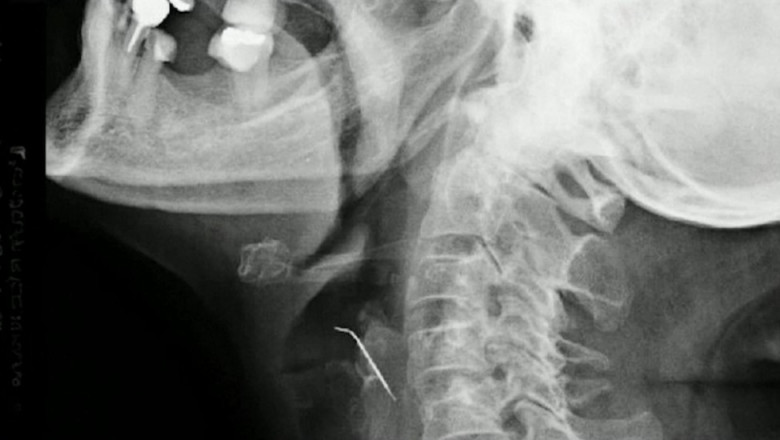

O femeie din Peru, în vârstă de 68 de ani, a ajuns de urgență la spital după ce a înghitit un obiect în timp ce mânca jumări de porc. După 43 de zile, femeia a fost operată de urgență, iar medicii au descoperit un cui lung de 5 centimetri în gâtul acesteia.

Femeia a fost operată imediat, iar medicii au făcut o descoperire șocantă - un cui lung de 5 centimetri în gâtul acesteia, care se afla într-una dintre arterele carotide. Această situație extrem de rară și periculoasă a necesitat o intervenție chirurgicală complexă pentru a salva viața pacientei.

"Ea a fost norocoasă că a ajuns la spital la timp, înainte de a suferi un accident vascular cerebral. Cuiul i-a străpuns artera și putea avea consecințe fatale", a declarat unul dintre medicii implicați în operație.